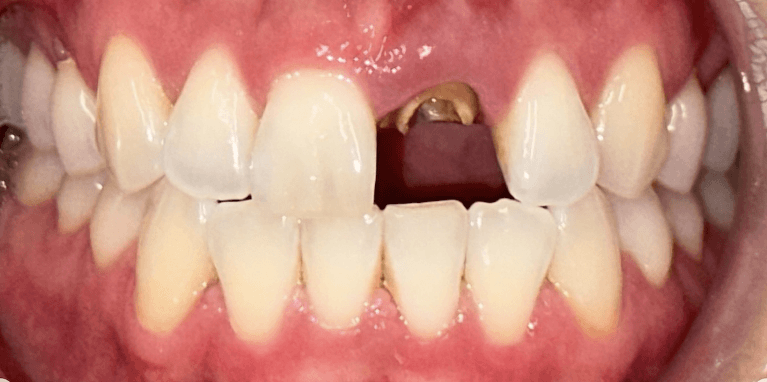

Broken Upper Central incisor with root canal replaced with Immediate implant after extraction.